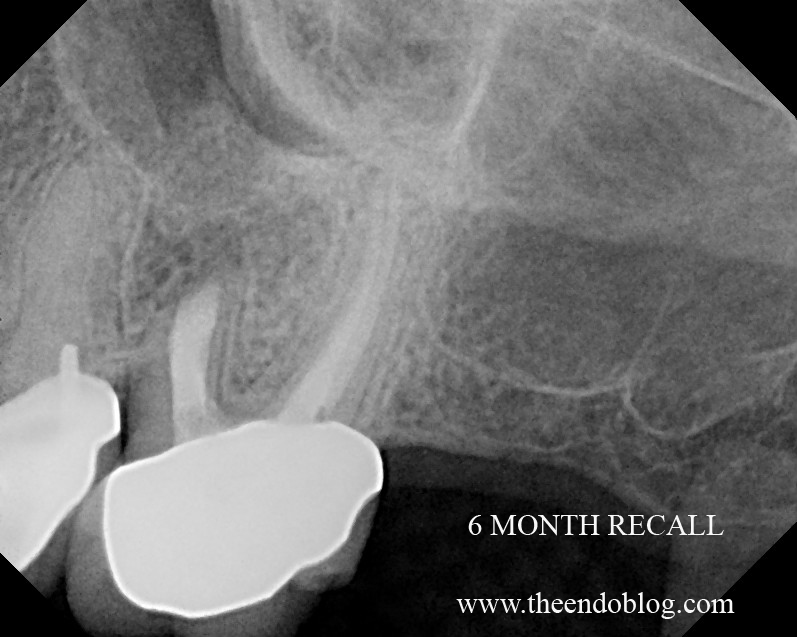

From www.theendoblog.com